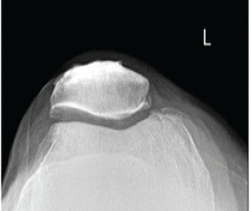

Letter to the Editor: Revisiting the “Ice Cream Scoop” Sign in Adult Elbow Tuberculosis: Extending Beyond the Pediatric Population

Nadeem Akhtar Qureshi

………………………………p.555-556